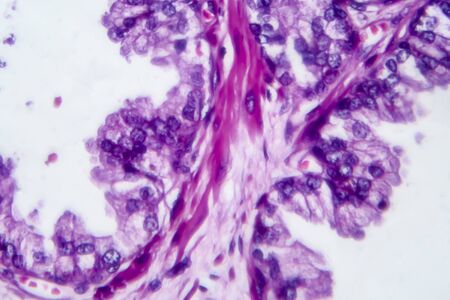

Bowen's Disease Tumor under the microscope 100x

Bowen's Disease Tumor under the microscope 100x